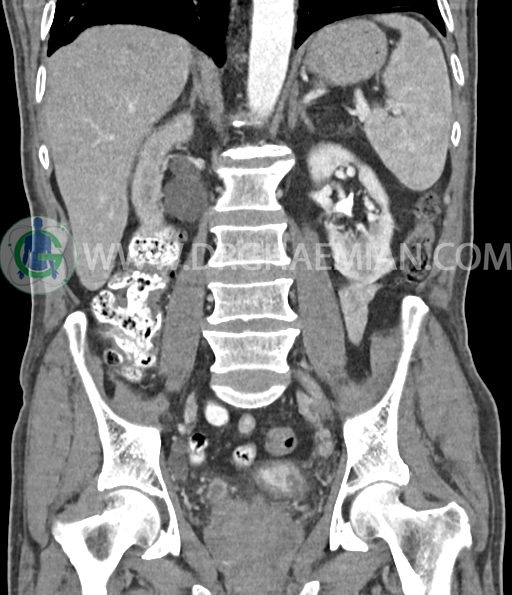

سی تی اسکن لگن و شکم از تشعشعات برای ایجاد تصاویر عرضی مقطعی از لگن و شکم استفاده می کند. در این کیس سرطان سلول انتقالی کلیه، ضایعه کبدی، دیورتیوکولوز، کیست کورتیکال در کلیه چپ، پروستات بزرگ شده، افزایش ضخامت دیواره مثانه دیده می شود.

در سی تی اسکن اسپیرال شکم و لگن با و بدون کنتراست خوراکی و وریدی (مولتی دیدکتور 16 با مقاطع ظریف و بازسازی های ساژیتال و کرونال) :

ضایعه کبدی هیپودنس بسیار کوچک به قطر 6mm در سگمان 7 لوب راست کبد مشهود است که با توجه به سایز بسیار کوچک ان در سی تی اسکن به خوبی کارکتریزه نمی شود.

دیورتیکولوز خفیف پراکنده بیشتر در کولون نزولی رویت شد.

کیست کورتیکال به قطر 15mm در پل تحتانی کلیه چپ دیده می شود.

افزایش ضخامت جداری و نامنظمی و لوبولاسیون همراه باenhancement مطرح کننده انفیلتراسیون و ضایعات تومورال در سمت راست ناحیه ترایگون و دیواره لترال راست مثانه دیده می شود که باعث اتساع حالب راست و هیدرونفروز moderate در کلیه راست شده است . این یافته های می توانند مطرح کننده TCC باشند .fat stranding در اطراف مثانه مشهود است. بیرون زدگی توده مانند به قطر 18mm در سمت راست ناحیه ترایگون دیده می شود که می تواند مطرح کننده گسترش اکسترا وزیکولر تومور باشد . لنفادنوپاتی با SAD=10mm درlevel ایلیاک داخلی چپ رویت شد . لنف نود دیگر با SAD= 5mm در همین ناحیه مشهود است. با توجه به این یافته ها stage احتمالی تومور T3، N1 or N2 می باشد .